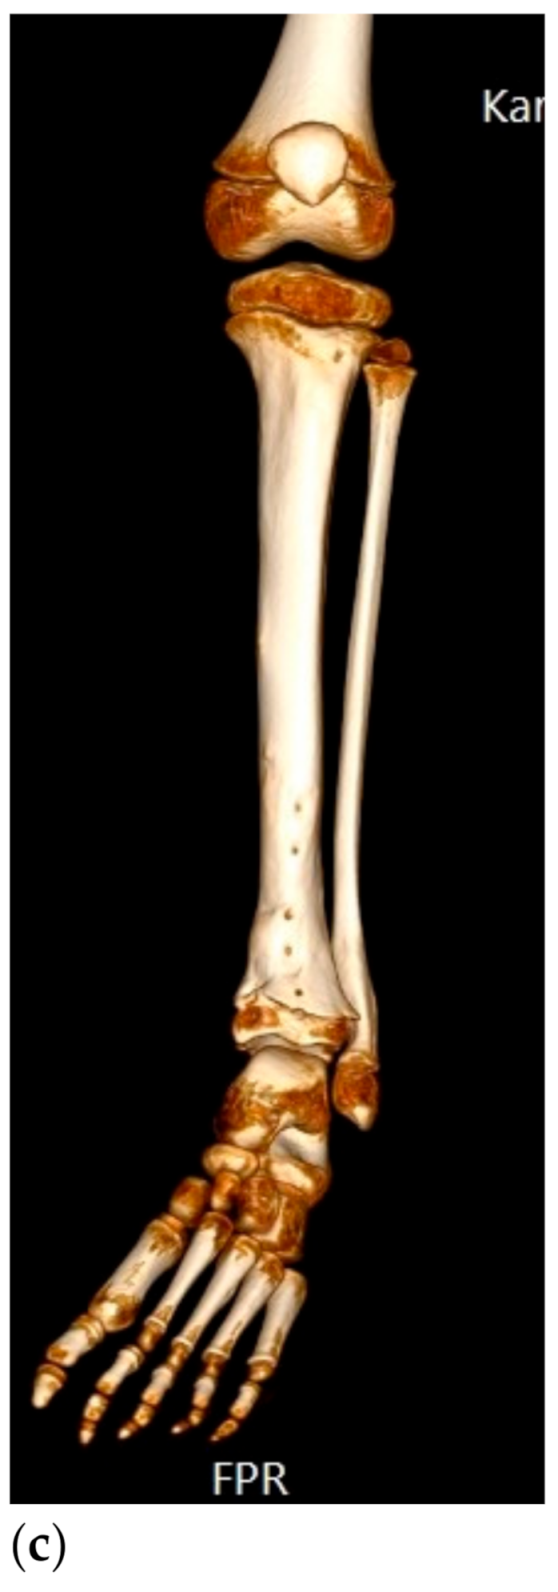

Figure 2.

Surgical failure of biological reconstruction after major pelvic surgery, salvaged with endoprosthesis. (a,b) A previously healthy 15-year old girl with 1-year history of left-sided groin pain. MRI of the pelvis (T1 TIRM coronal (a) and axial (b) images) showing a bone tumor involving the left superior ramus of the pubic bone and the periacetabular region of the iliac bone. There is a soft tissue component engaging the obturator internus-externus and adductor muscle. Staging procedures did not show any evidence of metastatic disease. Fine-needle aspiration showed a monotonous small round blue-cell tumor most likely representing Ewing sarcoma. FISH analysis showed an EWSR1-Fli1 fusion transcript confirming the Ewing sarcoma diagnosis. (c,d) After induction chemotherapy with VIDE (vincristine, ifosfamide, doxorubicin, and etoposide), the soft tissue component, as well as the intraosseous extension of the tumor, was significantly reduced, as shown on the coronal (c) and axial (d) T2 TSE FS MRI images. (e) The patient underwent a P2/P3 internal hemipelvectomy, extra-corporeal irradiation with 55 Grey and re-implantation of the autograft. (f,g) One year after primary surgery, the autograft collapsed (f), requiring salvage reconstruction with the Mutars Lumic Cup (g). A year later, the patient is functioning well and remains free of disease.